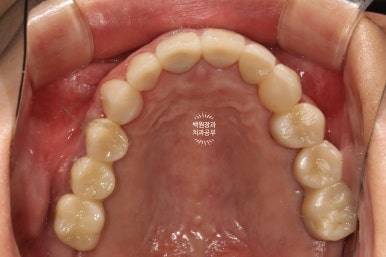

처음에 계획했던 5개의 어금니 임플란트와 3개짜리 지르코니아 브릿지 완성 후 정면 사진입니다.

아주 깔끔하게.... 정말 이상적으로 완성된 것을 보실 수 있습니다.

제 자랑 중입니다. 저희 한남동 분들도 모시기 위해 홍보중..

교합면에서 촬영한 것을 보면, 다수의 치야가 완성되어 드뎌 원래 치아가 있었던 상태로 돌아간 것을 보실 수 있어요.

치료 전 후 비교시 더욱 극적인 변화를 느끼실 수 있을겁니다.